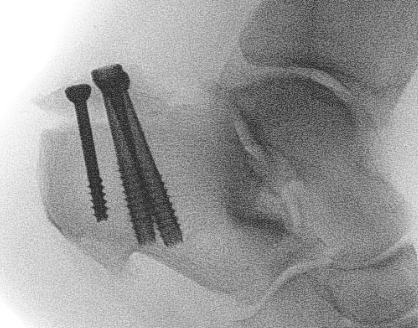

Xrays

Screw fixation

Poor bone quality

- 2 - 3 screws

- bicortical fixation

- fully threaded screws for extra fixation

- consider washers

- dont but screw heads too close to each other or fracture (risk of comminution)

Fixation failure with screws